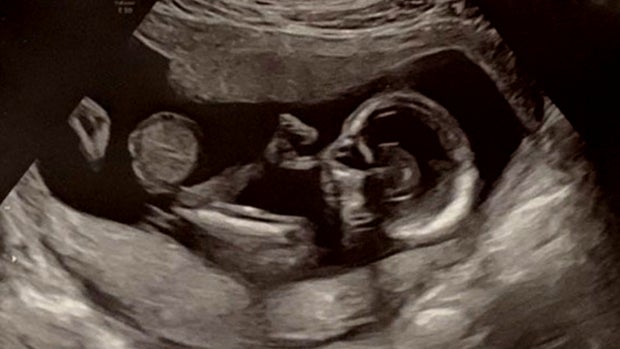

Little Bella came into the world with an omphalocele, a hole in the abdominal wall. Her liver and part of her bowel were in a nearly transparent sac poking out of her belly.

The problem was detected on an early ultrasound. Katherine and Aaron Beach were devastated.